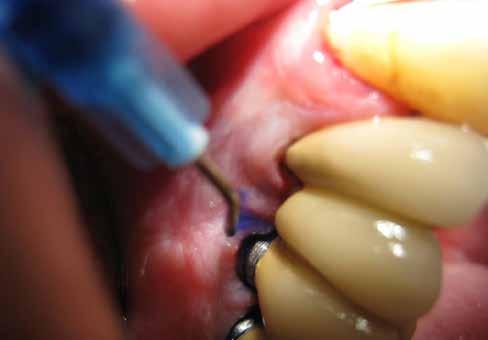

Ennek a beavatkozásnak az a célja, hogy az alkalmazásával szignifikáns mértékben csökkentsük a tasakokban jelenlévő baktériumok számát. A lézerek alkalmazásának nagyon fontos szerepe van a fibroblastok és a gingivális hámtapadás regenerációjának elősegítésében. A szakirodalomban találhatunk néhány vizsgálatot, amelyek eredményei azt bizonyítják, hogy a lézerek nem-sebészi célú alkalmazásával meg tudjuk változtatni a gingivális fibroblasztok aktivitását, ami a növekedési faktor mRNS-ének termeléséhez vezet. Az ilyen célú felhasználás révén elő tudjuk segíteni a parodoncium regenerációját. A szövetek hatékonyabb gyógyulásának további elősegítésének érdekében a kezelést biostimulációval folytatjuk. Ezt egy a lézerhez csatlakoztatható speciális toldalék segítségével végezzük el. A lézert 60 másodpercen keresztül 1 W-os teljesítmény mellett alkalmazzuk (14. a–b ábra). A LAFMD protokoll kifejezett mértékben alkalmas a parodontális betegségek egy speciális formájának, a peri-implantitisnek a kezelésére.

Tudományos eredmények igazolták, hogy jobb rövid távú eredményeket lehet elérni a peri-implantitis kezelése során, ha olyan kezelési protokollokat alkalmazunk, amelyek magukba foglalják a diódalézerek alkalmazását. Azok a protokollok, amelyekben nem szerepelt diódalézerrel végzett kezelés, kevésbé voltak hatékonyak. Ennek megfelelően a peri-implantitissel érintett területek fertőtlenítése és kezelése során, a cikkünkben leírt kezelési protokoll alkalmazása hasznos segítséget jelenthet a terápia során. Mivel a protokoll elvégzését követően 6 hónappal végzett vizsgálatok a bakteriális flóra részleges rekolonizációját igazolták, ezért a

A kezelés e szakaszának a befejezésekor a gyulladásos tünetek hiánya, a csökkenő tasakmélység és a szondázást követő vérzés megszűnése megfelelő bizonyítékul szolgálhat az eddig elvégzett beavatkozások hatékonyságára (15. ábra). A páciensek idővel képesek lesznek ennek az állapotnak a fenntartására, ha a fogorvosok által adott instrukcióknak megfelelően végzik a napi szájhigiénés tevékenységüket, és ha ebben megfelelően támogatják őket.